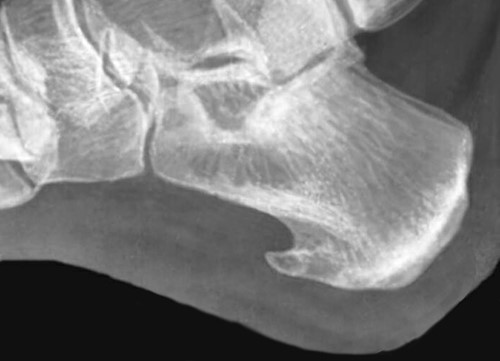

Пяточная шпора (плантарный фасциит) – выглядит как костные наросты в виде шпоры или шипа на подошвенной части стопы. При передвижении шип давит на окружающие ткани провоцируя развитие болевого синдрома. В среднем размеры шпоры обычно составляют 0,5-1,2 см. В медицине такой нарост называют – экзостоз.

По статистике в большинстве случаев (около 90%) происходит изменение походки в силу того, что человек подсознательно пытается уменьшить неприятные болевые ощущения вызванные давлением шипа. В итоге при ходьбе человек пытается скомпенсировать движения и больше напоминает движение лыжника. Для точного определения необходим рентген и обследование с помощью аппарата УЗИ, а также анализы крови и мочи. Целью этого является не только постановка правильного диагноза, но и выяснение причины вызвавшей развитие болезни.